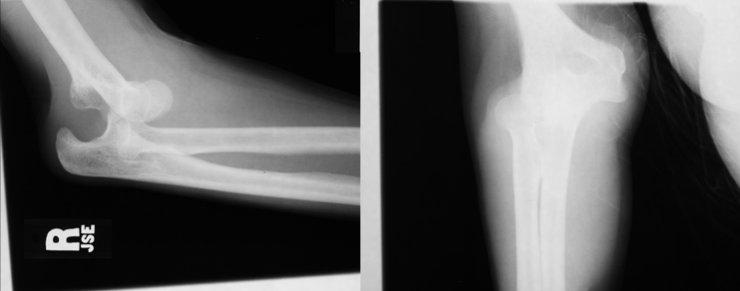

7

Q

What is the diagnosis?

What radiographic sign is present?

A

Intracapsular fracture with effusion/lipohemarthrosis

FBI sign present

8

Sail sign present